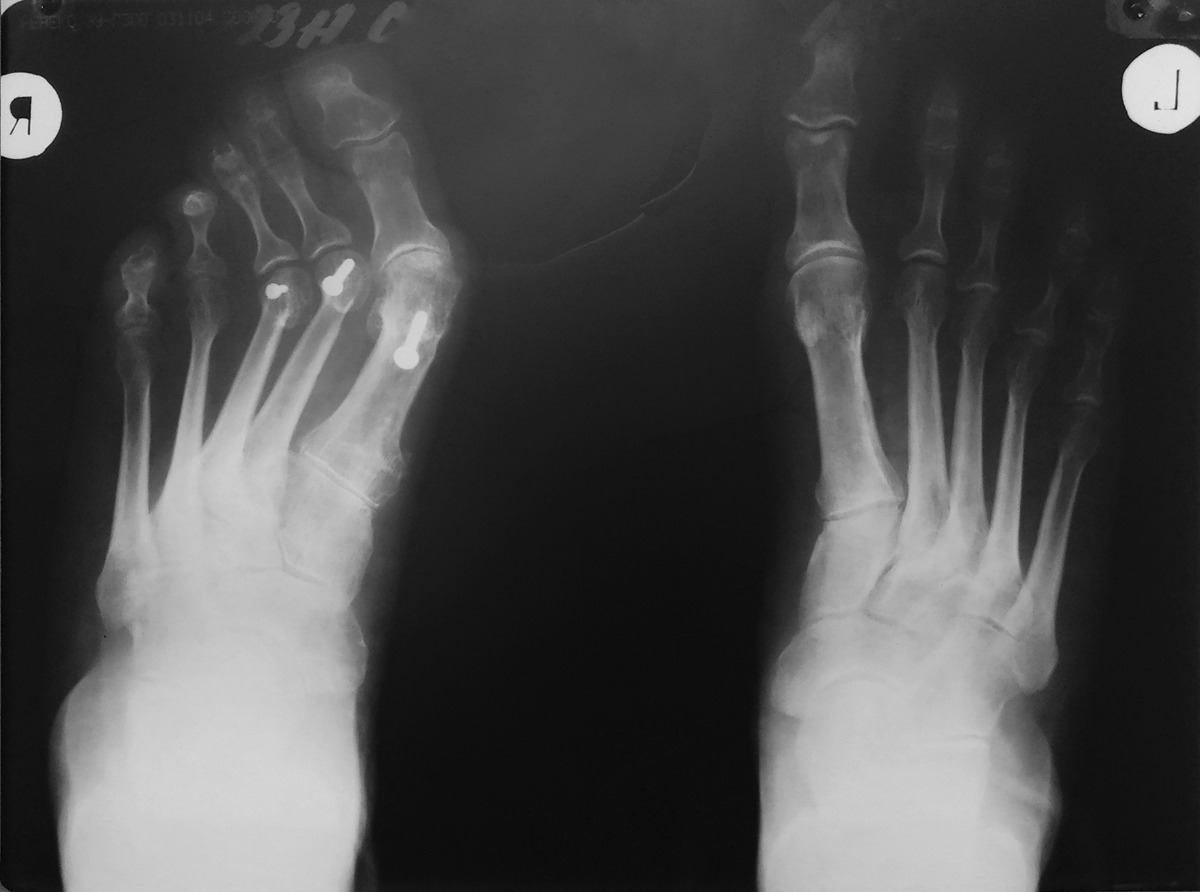

Больная С., 53 года, бухгалтер. Оперирована в 2010 году (выписки нет), в 2011 году (SCARF), в 2012 году (+Weil 2 и 3 плюсневых, артроэрез), в 2013 году (удаление винта). На данный момент беспокоит молоточкообразная деформация 5 пальца и "шишка" в области 1 ПФС. При пальпации - округлое мягкотканное образование с ровными и четкими контурами (бурсит). Рентгенограмм предыдущих нет, представленная от октября 2017 года. HV - 42 град., PASA - 27 град., DASA - 0 град., P1P2 - ротация пальца, М1М5 - 24 град.